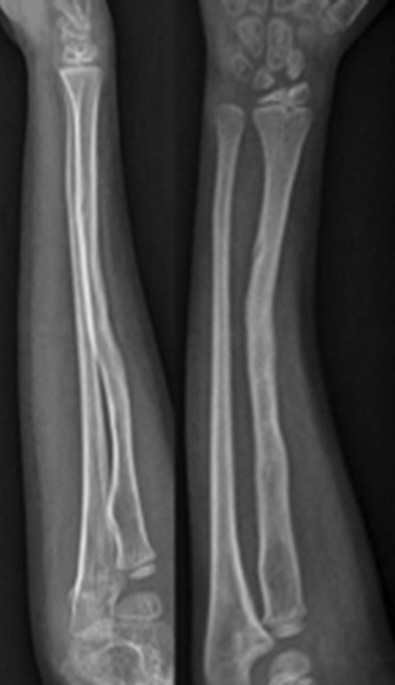

Клинически, как и по данным рентгенологического исследования, у пациента наблюдалось местное улучшение. Спустя 6 мес. после последней трансплантации спица Киршнера была удалена. При контрольном осмотре через 28 мес. у пациента зарегистрированы полная консолидация начального участка несращения, отсутствие нейроваскулярной недостаточности и суставной недостаточности. Больного можно считать выздоровевшим (рис. 7, 8).

Рис. 7. Рентгенограмма после удаления спицы Киршнера через 28 мес. после травмы